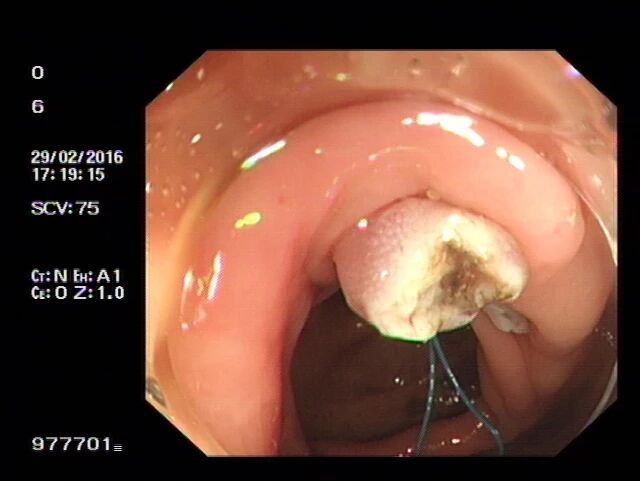

让我们通过肠镜下图片,来了解一下息肉切除的几个步骤:

步骤一:发现息肉,并将其暴露于视野正中。

步骤二:通过肠镜上的孔道插入特殊器械(电圈套器),并在息肉旁伸出钢丝圈。

步骤三:将钢丝圈套住息肉,并于息肉根部收紧钢丝圈。

步骤四:轻轻向肠腔内提起息肉,使钢丝圈尽量远离肠壁黏膜。

步骤五:在钢丝圈上脉冲式通高频电进行电灼烧,直至息肉根部被切断,息肉脱落。

步骤六:为防止创面迟发性出血,可以使用金属夹子夹闭创面。本图为夹子在创面旁打开。

步骤七:金属夹子于创面处夹闭。